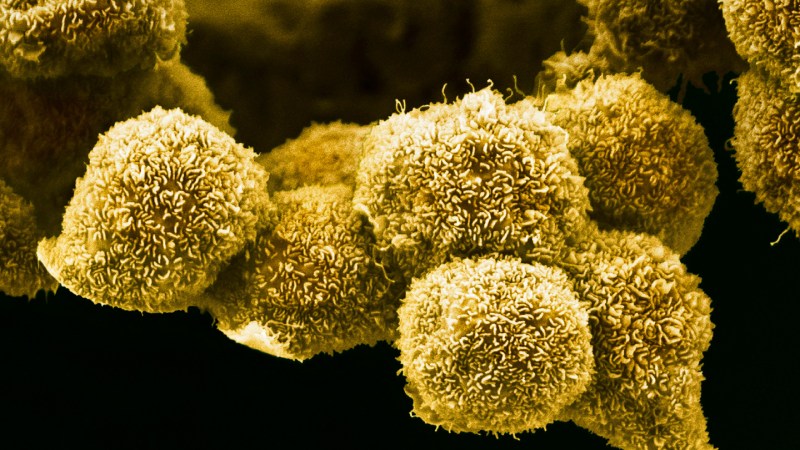

Why cancer spreads more in middle age than in old age

Cancer becomes more common with age and is often harder to treat in older adults. Yet most cancer studies in mice do not reflect that reality. Fewer than 10% of mouse experiments use aged animals, with researchers typically relying on mice that…